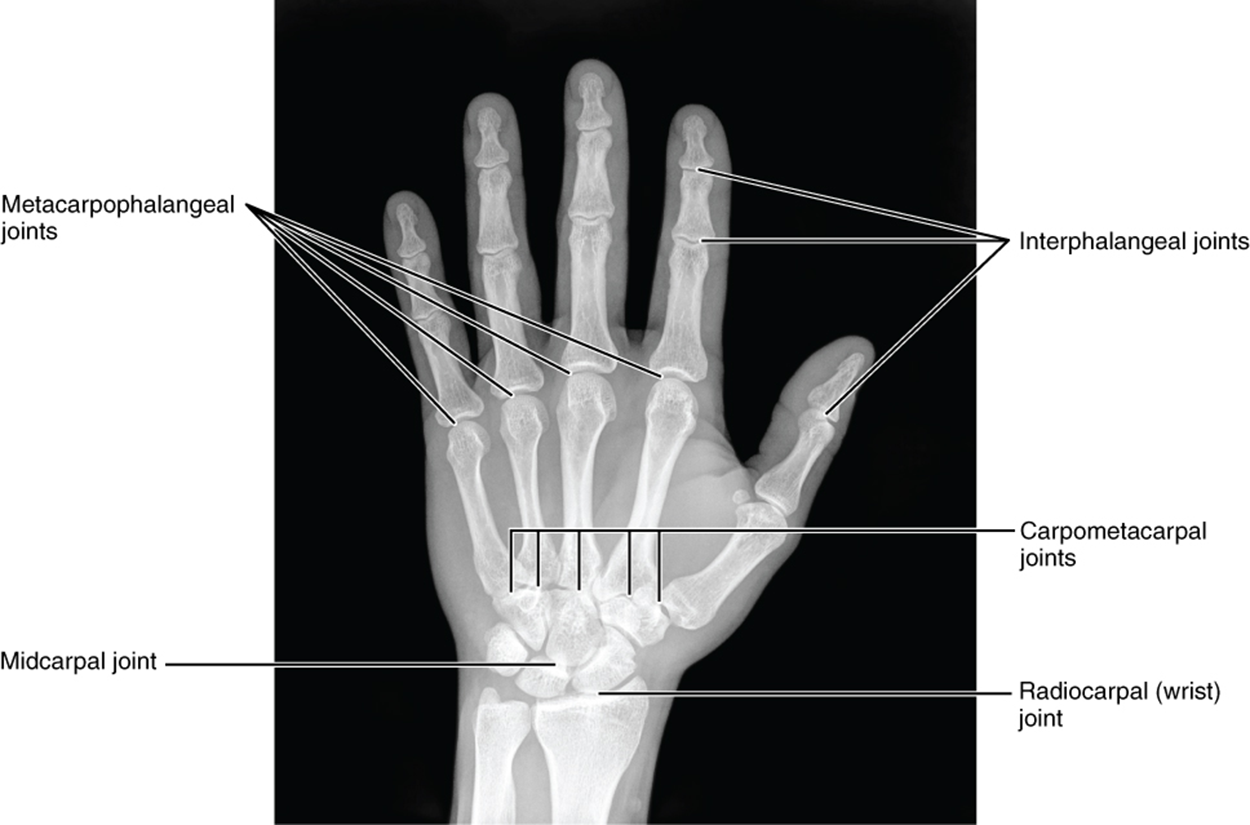

The carpal bones form the base of the hand. This can be seen in the radiograph (X-ray image) of the hand. These bones form several joints. The radiocarpal joint is formed between the radius and three of the four proximal carpal bones—the scaphoid, lunate, and triquetrum. The ulna does not directly articulate with the carpal bones. However, through a fibrocartilaginous pad, the ulnocarpal joint is formed between the ulna and two of the four proximal carpal bones—lunate and triquetrum.

The proximal and distal rows of carpal bones articulate with each other to form the midcarpal joint. Together, the radiocarpal and midcarpal joints are responsible for all movements of the hand at the wrist. The distal carpal bones also articulate with the metacarpal bones of the hand.

This image shows a radiograph of a human hand.

Bones of the Hand - This radiograph shows the position of the bones within the hand. Note the carpal bones that form the base of the hand. Credit: modification of work by Trace Meek

The palm of the hand contains five elongated metacarpal bones. These bones lie distal to the carpal bones of the wrist (meta, after) and proximal to the bones of the fingers and thumb. The proximal end of each metacarpal bone articulates with one of the distal carpal bones. Each of these articulations is a carpometacarpal joint. The expanded distal end of each metacarpal bone articulates at the metacarpophalangeal joint with the proximal phalanx bone of the fingers. The distal end also forms the knuckles of the hand, at the base of the fingers. The metacarpal bones are numbered 1–5, beginning on the lateral (thumb) side.

Each digit contains multiple phalanges, which are named based on their numerical digit and the distance from the palm—proximal, middle, or distal. The thumb is digit number 1 and has two phalanges, a proximal phalanx, and a distal phalanx bone. Digits 2 (index finger) through 5 (little finger) have three phalanges each, called the proximal, middle, and distal phalanx bones. An interphalangeal joint is one of the articulations between adjacent phalanges of the digits.